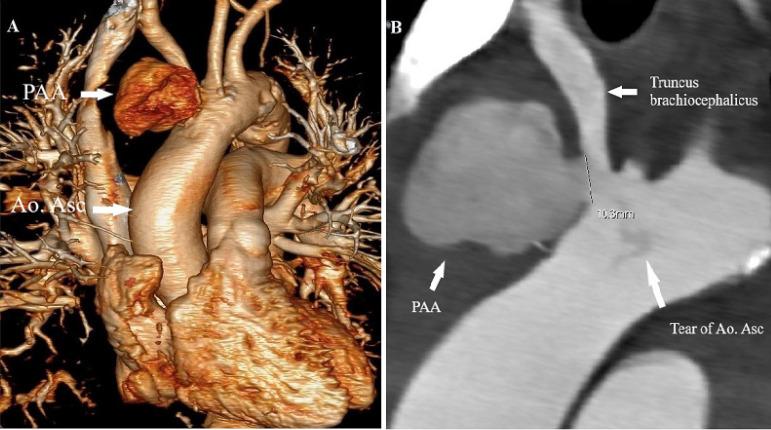

Pseudoaneurysm of the ascending aorta (PAA) is a hazardous and potentially fatal cardiovascular disease. This condition is caused by the rupture of at least one layer of the vessel and contained by the remaining vascular layers or the surrounding mediastinal structures. We presented the surgical treatment of a patient with sepsis and large PAA and brachiocephalic trunk, which was compressing the brachiocephalic trunk leading to syncope.

升主动脉假性动脉瘤(PAA)是一种危险且潜在致命的心血管疾病。这种情况是由至少一层血管破裂,由剩余的血管层或周围的纵隔结构所包含引起的。我们介绍了一例脓毒症和大型 PAA 及头臂干患者的手术治疗,该患者的头臂干受到压迫导致晕厥。